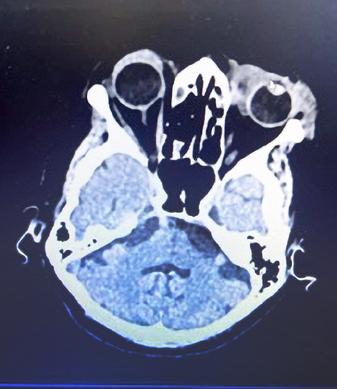

O femeie de 79 de ani COVID+ s-a deplasat la secția de Oftalmologie cu colecție fistulizată în treimea interioară a polului anterior a pleoapei inferioare. Inițierea tratamentul s-a efectuat cu Cefort 1 gr și Gentamicină 80 mg și antiinflamatoare. Examenul CT a evidențiat formarea chistică cu dimensiunile de 2,7/1,5 cm adiacent cantului medial al ochiului stâng cu extensie la nivelul canalului naso-lacrimal cu un calibru crescut. Datorită evoluției staționare s-a cerut consult în serviciul de Otorinolaringologie.

O femeie de 79 de ani s-a internat de urgență în Secția de Oftalmologie cu infecție SARS-CoV-2 pozitivă acuzând: edem periorbitar, cu motilitate oculară păstrată, fără diplopie, fără exoftalmie, fără chemozis, secreții purulente în sacul conjunctival, cornee transparentă, pupila rotundă centrală, iris cu model radial, cataractă corticonucleară, canale lacrimale nepermeabile. Abcesul a fistulizat exterior în treimea interioară a polului anterior al pleoapei inferioare asociind hiperemie și

edem palpebral. Antecedentele heredocolaterale evidențiază un istoric de hipertensiune arterială și un cancer mamar operat radiotratat, care nu a fost relevant pentru strategia de tratament. Se inițiază un tratament antibiotic intravenos cu: Ceftriaxona 1 gr la 12 ore asociat cu Gentamicină 80mg/2ml la 12 ore, tratamentul local a fost asocierea de: Bethametazona și soluție Cloramfenicol (Betabioptal). După 24 de ore de tratament edemul pleoapei este remis dar rămâne un edem eritematos, indurat inferior (din unghiul intern spre treimea externă), fără chemozis, nedureros, mobilitate prezentă, fără diplopie în toate cadranele, restul polului de aspect normal. Pacienta a avut o stare generală bună, afebrilă, fără tulburări de motilitate vizuală și oculară. Nu au fost raportate antecedente traumatisme faciale. S-a efectuat un examen CT cerebral în urma căruia s-a evidențiat o formațiune chistică cu dimensiunile de 2,7/1,5 cm adiacent cantului medial al ochiului stâng cu extensie la nivelul canalului naso-lacrimal arătând un calibru crescut cu o densificare difuză asemănătoare celulitei a țesutului palpebral stâng și cu osteoliză la nivelul laminei papiracee. Pacienta a refuzat tratamentul SARSCoV-2 și, din cauza progresului staționar, a fost trimisă la secția de Otorinolaringologie pentru a doua opinie. Inițial s-a verificat permeabilitatea ductului naso-lacrimal, s-a schimbat tratamentul cu antibiotice Ceftriaxona cu Levofloxacina, s-a practicat o incizie la nivelul orificiului